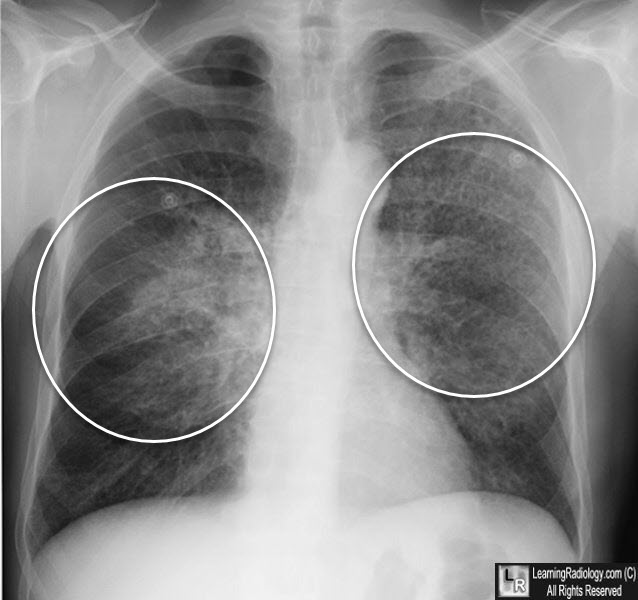

Рентгеновские снимки при пневмоцистной пневмонии